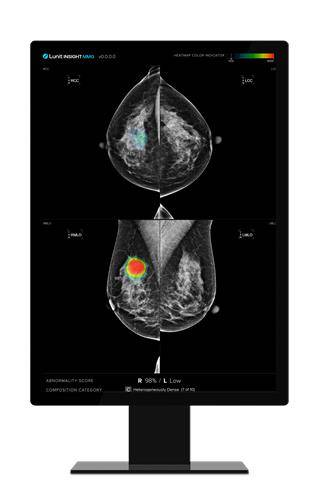

용인세브란스병원은 의료 AI 기업 루닛의 유방촬영술 AI 영상분석 설루션 '루닛 인사이트 MMG'를 사용하고 있다.

루닛 인사이트 MMG는 유방 촬영 영상을 분석해 유방암 등 의심 부위를 검출하는 설루션이다. 환자가 유방촬영술을 받으면 유방 사진이 의료진 측에 전달되는데, 루닛 인사이트 MMG는 해당 사진에 종양이나 석회 등 의심 부위를 동그랗게 표시해준다. 유방 치밀도도 분석한다.

이날 기자가 직접 유방촬영술을 받은 뒤 루닛 인사이트 MMG로 분석된 사진을 보자 유방 내 악성 병변 존재 가능성, 유방 치밀도 수준 등이 일반 환자도 알기 쉽게 직관적으로 표시된 것을 확인할 수 있었다.